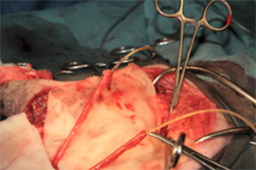

飼い主様の希望により、膀胱腫瘍切除ため膀胱全摘出および尿管の転移植手術を行いました。

取り出した膀胱の腫瘍です。

膀胱および前立腺も切除しました。

包皮粘膜に尿管を開口しました。

術後は包皮から排尿できるようになりました。膀胱の腫瘍は平滑筋肉腫と言われる膀胱の腫瘍の種類にしては珍しい腫瘍でしたが、完全に取りきれているとのことでした。現在術後1年以上経ちますが経過良好で過ごしています。